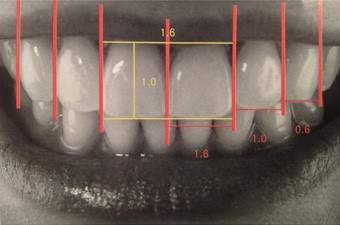

前歯の幅を「中切歯、側切歯、犬歯」の比率を「1.6:1:0.6」とすることで、より美しい口元になります。

正中線とは顔の中央を示すラインのことで、このライン上に上顎の前歯が整列すると、歯並びが全体的にバランスよく見えます。